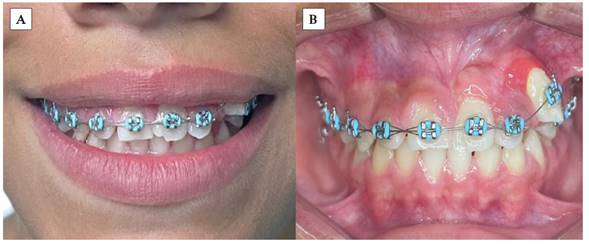

Al examen clínico inicial (Figura 1), se aprecia ausencia de unidad dentaria superior; y al examen radiográfico inicial (Figura 2), la radiografía panorámica muestra una falta de erupción del incisivo central superior izquierdo permanente (UD 21), con desviación hacia el mesial de canino superior izquierdo permanente (UD 23) sin erupcionar, en íntimo contacto con la raíz del incisivo lateral izquierdo permanente (UD 22). Se puede apreciar presencia de zona radiolúcida en tercio incisal de la UD 21, presuntamente asociada a un defecto del desarrollo del esmalte, específicamente hipoplasia de esmalte. Presenta un patrón de exfoliación dental acorde a la edad en el sector inferior, etapa 8 de Nolla.

Inicialmente, se realizó la exodoncia del canino primario superior izquierdo para mejorar el corredor de erupción del incisivo central superior permanente. En la fase de ortodoncia inicial se coloca la aparatología fija con prescripción de Roth slot 0,22, exclusivamente en las UD 24, 25 y 26, además de un minitornillo como anclaje absoluto en la zona molar izquierda para tracción distal del canino superior (UD 23) y evitar así mesializaciones no deseadas al consolidar dicho sector. Al ubicar la UD 23 en su posición correcta, la UD 21 erupcionó posterior a destrabar ese espacio. Después de observar que dicha unidad dentaria iba erupcionando, se realizó un ojal quirúrgico y se cementó un bracket en la UD 21 y en el resto de la arcada superior para continuar con los pasos de alineación y nivelación, siguiendo la secuencia de arcos con normalidad en la ortodoncia correctiva (Figuras 4 y 5).

Al tener los dientes en su correcta disposición, se apreció que el paciente presentaba una topografía gingival asimétrica, por lo que se procedió a realizar gingivectomía y gingivoplastia del sector anterosuperior para obtener un contorno más estético y fisiológico del tejido blando (Figura 6). Siguiendo un orden, se observa un exceso de encía queratinizada en algunas unidades dentarias; por ejemplo, en la UD 23 se identifica una banda muy estrecha. Además, es necesario realizar ajustes en la estética dental para armonizar la anatomía dentaria, lo cual también repercute en la evaluación de los parámetros estéticos.